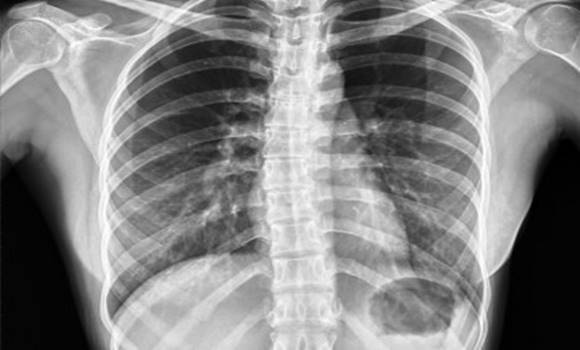

Kevésbé gyakori, de súlyosabb ok a tüdőgyulladás, szívburokgyulladás, májmegnagyobbodás, epehólyag-

gyulladás. Előfordul, hogy a vérben lévő káros anyagok – például a veseelégtelenségben felhalmozódó

salakanyagok – okozta rekeszizom-izgalom áll a háttérben.

Ritkán agytumor vagy szélütés ingerli a légzőközpontot, és ez okoz csuklást. Az American Cancer Society orvosi szaklap szerint a kemoterápiával kezelt betegek 30%-ánál is fellép csuklás.